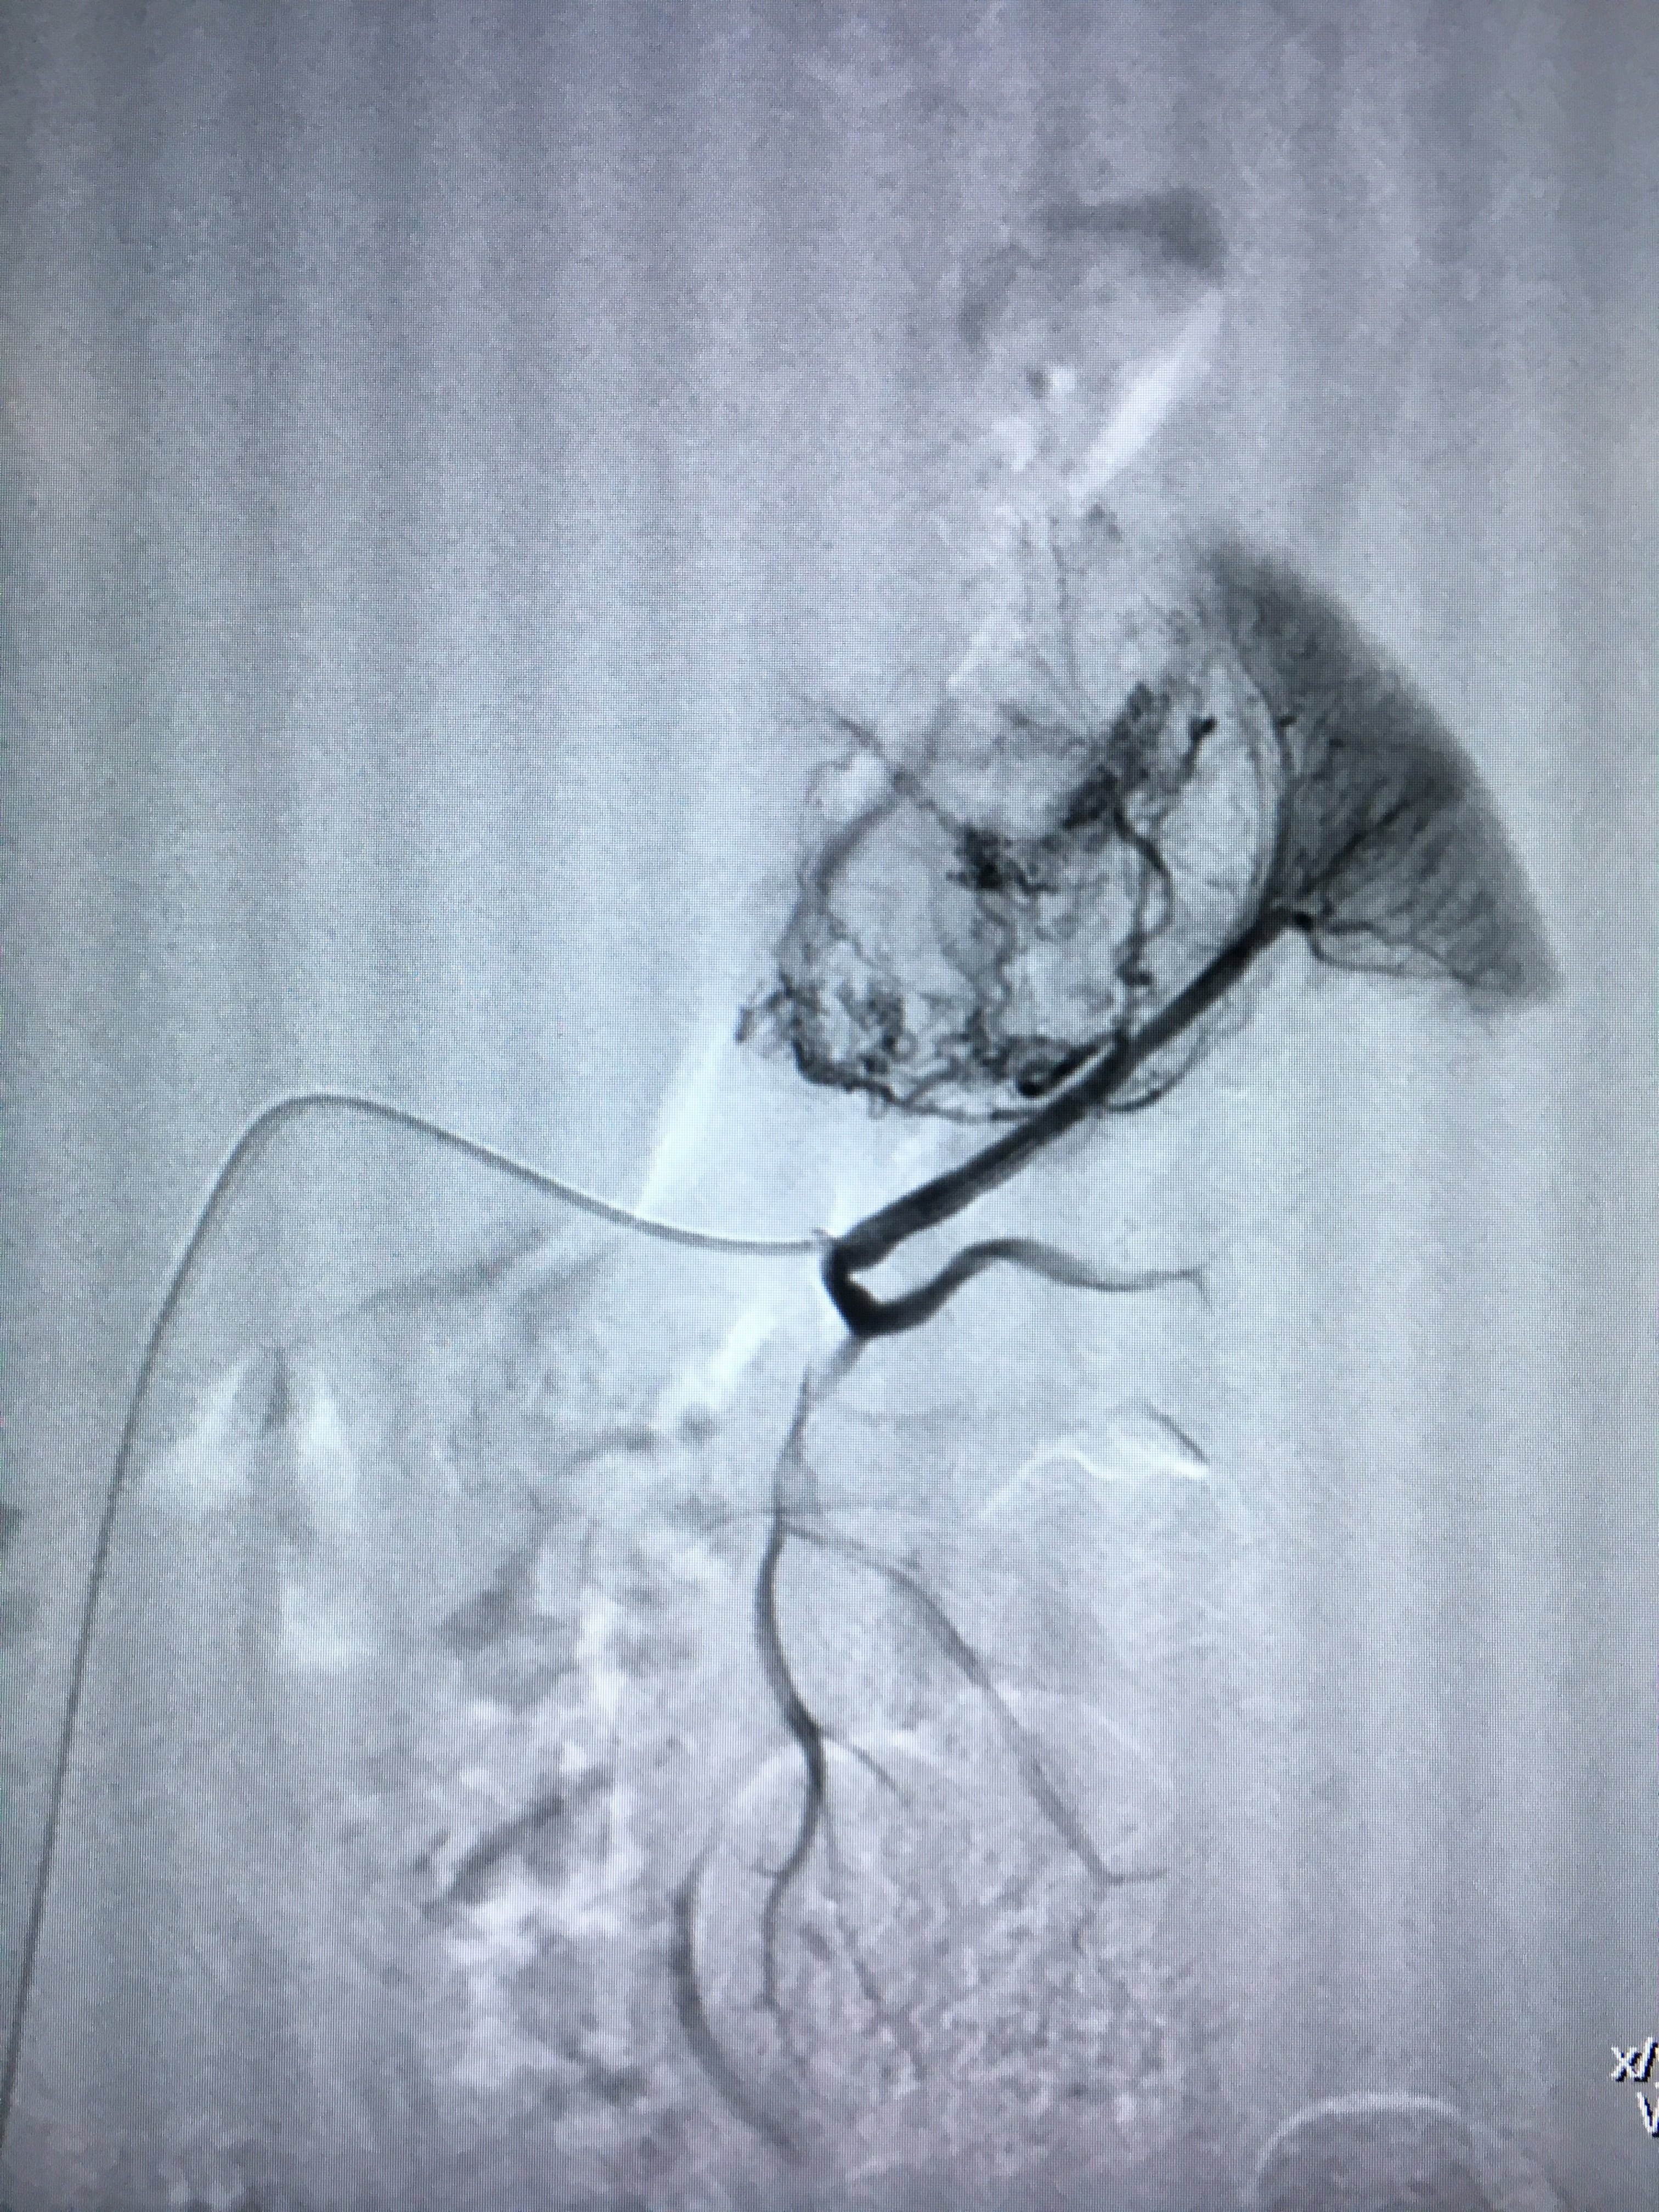

介入栓塞治疗肾脏巨大错构瘤破裂出血

肾错构瘤介入治疗